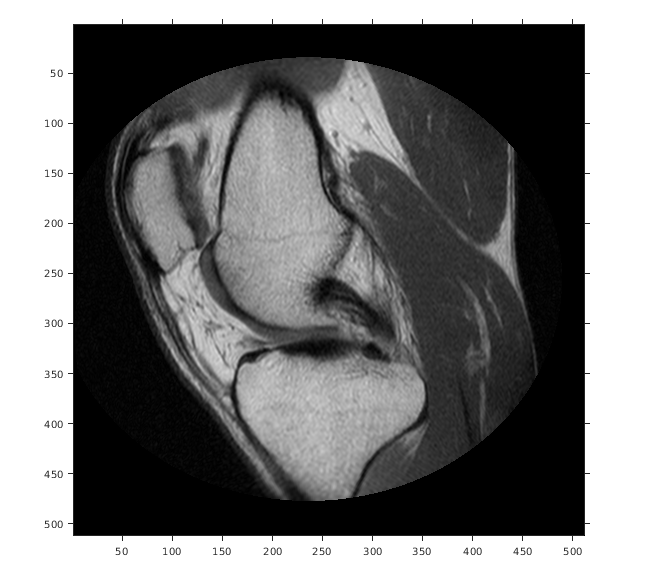

Считайте 2D полутоновое изображение в рабочую область.

m = dicominfo('knee1.dcm');

A = dicomread(m);

Создайте imref2d объект, задавая размер и разрешение пикселей. Файл DICOM содержит поле метаданных PixelSpacing это задает разрешение изображения в каждой размерности в миллиметрах на пиксель.

RA = imref2d(size(A),m.PixelSpacing(2),m.PixelSpacing(1))

Отобразите изображение, не использовав пространственный объект привязки. Координаты осей отражают внутренние координаты. Заметьте, что координата (0,0) находится в левом верхнем углу.

figure

imshow(A,'DisplayRange',[0 512])

axis on

Предположим, что вы хотите вычислить аппроксимированное положение и ширину колена в миллиметрах. Выберите конечные точки линейного сегмента, который запускается горизонтально через колено на уровне коленной чашечки. Например, используйте (x, y) точки (34,172) и (442,172).

xIntrinsic = [34 442];

yIntrinsic = [172 172];

Преобразуйте эти точки от внутренних координат до мировых координат.

[xWorld,yWorld] = intrinsicToWorld(RA,xIntrinsic,yIntrinsic)

xWorld = 1×2

10.6250  138.1250

yWorld = 1×2

53.7500   53.7500

Мировые координаты двух точек (10.625,53.75) и (138.125,53.75) в модулях миллиметров. Аппроксимированная ширина колена в миллиметрах:

width = xWorld(2) - xWorld(1)

width = 127.5000